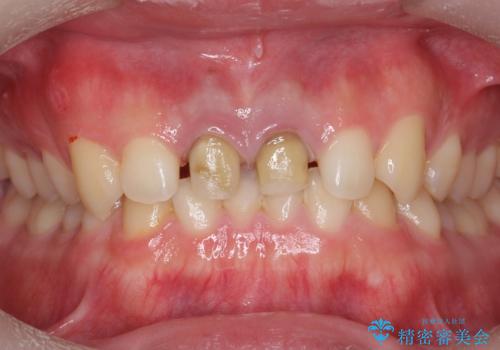

前歯の変色 神経のない歯の再治療

- 前歯の変色を気にして来院。

過去に神経の治療を行ったとのことでした。

特に右上の前歯の膿は大きくなって歯ぐきから排膿している状態でした。(フィステルといいます)

二本とも神経の治療のやり直し(再治療)を行ってからセラミックを入れています。